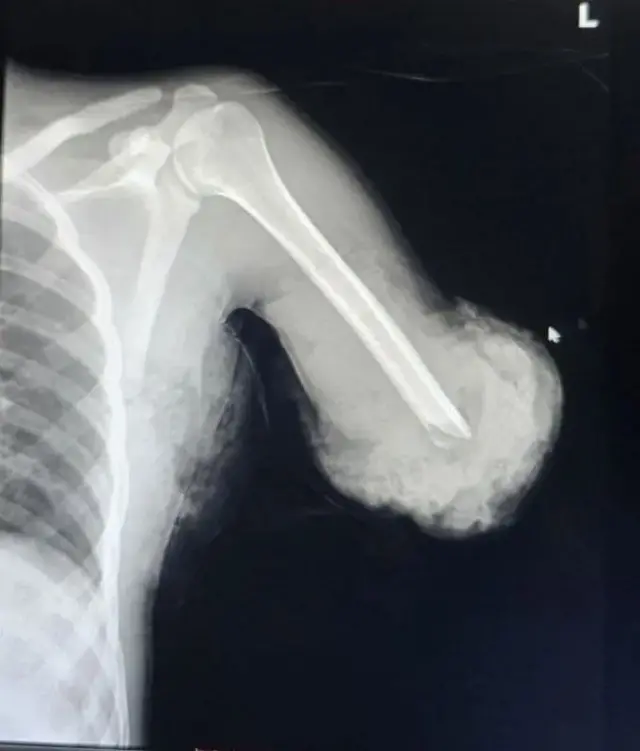

Dr Anteneh Hailu, umuganga w'inzobere ku bitaro byigenga bya Samaritan Surgical Center i Addis Ababa yabwiye BBC ko ukuboko kw'umusore kwari kwacitse kukava ku mubiri mu mpanuka kwasubijweho neza mu kugaba gukomeye uyu murwayi yakorewe.

Abaganga muri icyo gihugu banuganuga ko iki ari cyo gikorwa cyo kubaga mu gusubizaho urugingo "cya mbere kigenze neza" muri Ethiopia.

Dr Anteneh yasobanuye ko mu byumweru bitatu bishize umusore w'imyaka 20 yakiriwe kuri ibyo bitaro nyuma y'uko ukuboko kwe guciwe n'imashini ikata imbaho aho akorera.

"Ukuboko kwe kwacikiye hejuru y'inkokora. Kwari kwavuyeho kwatandukanye n'umubiri", ni ko uyu muganga yavuze.

Dr Anteneh Hailu yasobanuye ko abantu bamwe bajya bakorerwa kubagwa guto nko mu gihe intoki zabo ziri mu kaga ko gucibwa; "ariko uku kwari ugucika gukomeye. Aho umurwayi n'igice cy'umubiri we byahageze bitandukanye", nk'uko abivuga.

Dr. Anteneh avuga ko uko kubaga kugoye cyane kwamaze igihe kinini gukorwa n'inzobere enye zo mu bice byihariye kandi bitandukanye by'ubuvuzi.

Hejuru y'ibyo uko kubaga, kwasabye kwitonderwa ku gipimo cyo hejuru, kwakozwe mu byiciro bibiri.

Icyiciro cya mbere cyamaze amasaha atandatu, icyiciro cya kabiri cyo kubaga cyakozwe nyuma y'ibyumweru bibiri na cyo kimara hafi amasaha atandatu.

Mu kubaga, "hibanzwe cyane cyane ku gusubiranya igufa n'imitsi y'ibanze itwara amaraso, iyo mitsi yongeye guhuzwa kugira ngo akaboko kari kacitse kongera gukora.

"Inzobere zanzuye ko nyuma yo gusubiranya imitsi, n'igufa, udutsi duto n'imikaya byo bihabwa igihe bigakorwaho nyuma, nuko kubagwa bigakorwa mu byiciro."

Dr Anteneh, wemeza ko igufa ryacitse ryongera rigasubirana iyo rihujwe, yanasobanuye ko imitsi itwara amaraso na yo yongera igahuzwa igice cyari cyavuyeho kikongera kubona amaraso.